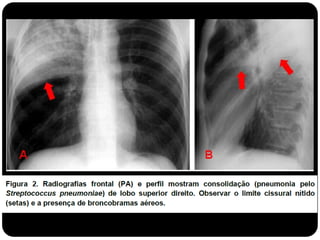

Padrão Alveolar

Adenocarcinoma de pulmão

apresentando-se como padrão

acinar;

Atelectasia do Lobo Sup. D. (compare com slide

anterior que era consolidação de LSD!)

Conceitos

 Atelectasia: ausência do ar alveolar;

 Consolidação: substituição do ar alveolar (não há redução de

volume);

 Quando ocorre essa consolidação os brônquios em seu

interior podem tornar-se visíveis – broncograma aéreo.